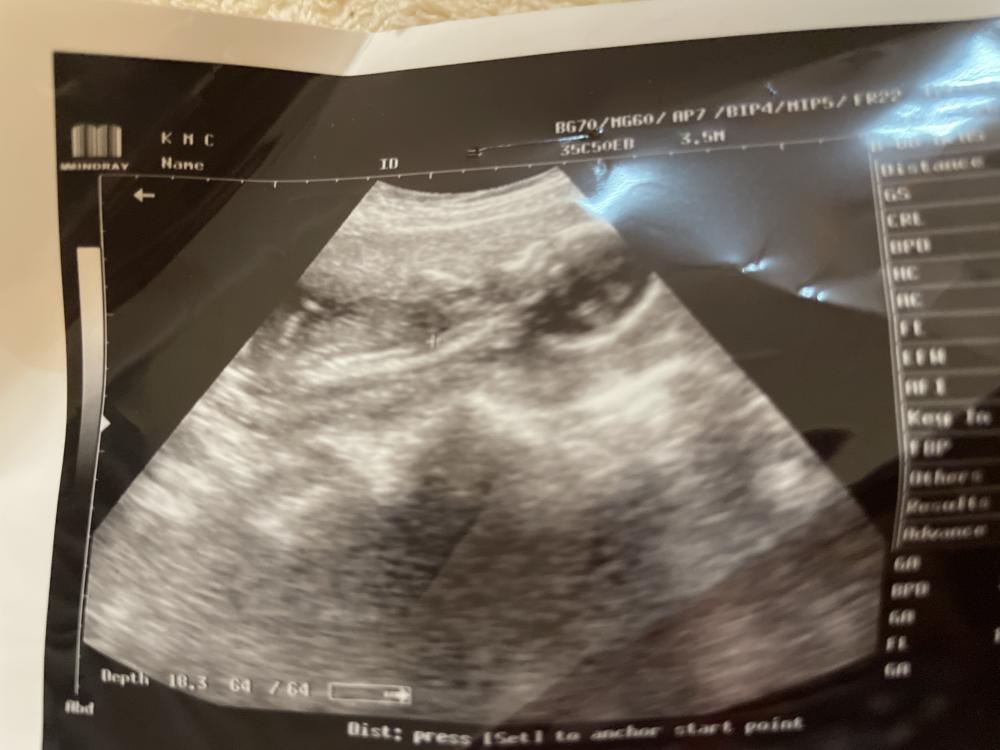

انا رحت اليوم وسويت سونار قالتلي احتمال بنت بس ما متاكده مع انه احساسي ولد 🤣

هذا السونار اليوم حاولت افهم بس ما فهمت 😂😂😂